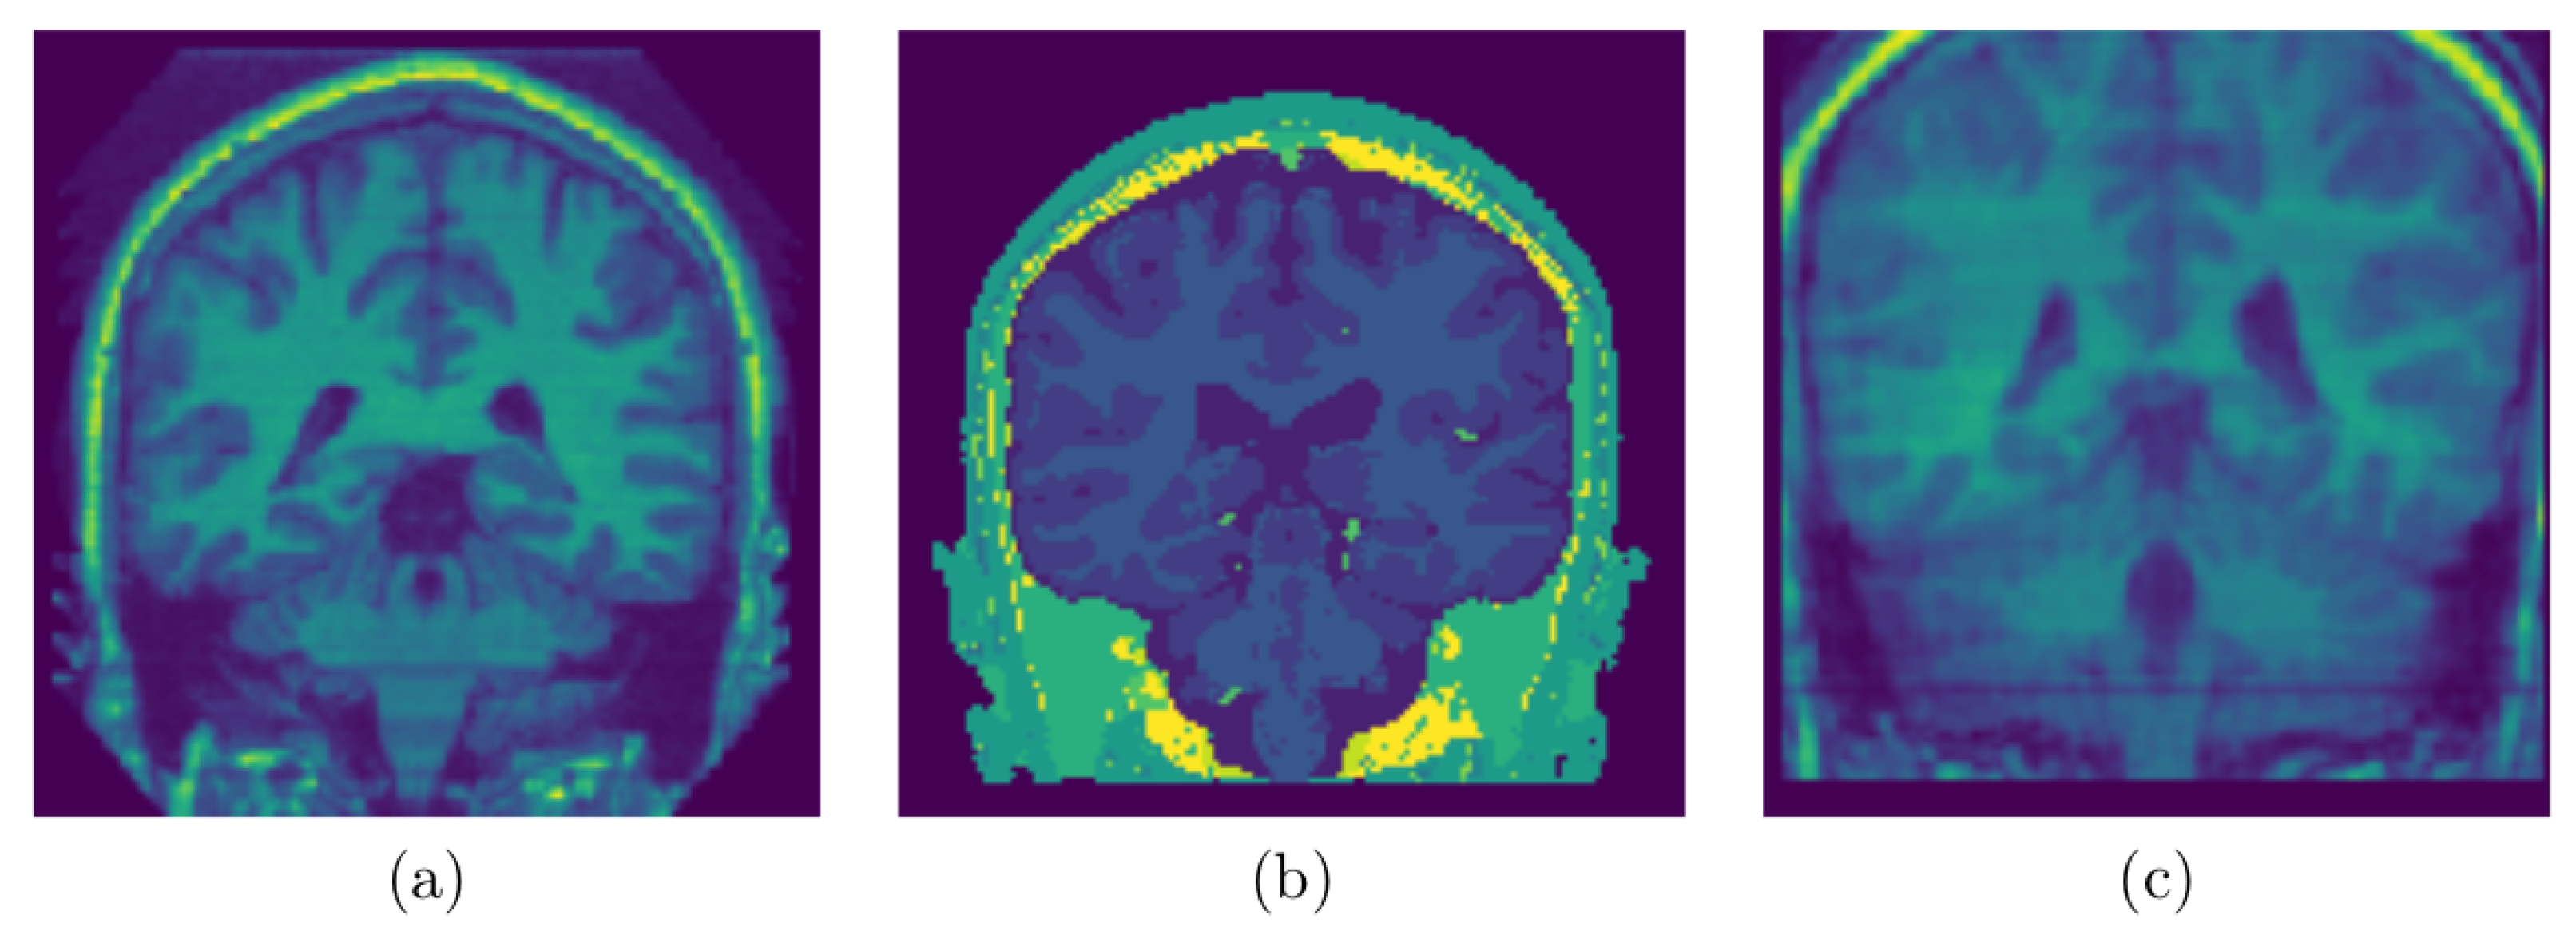

2.2.2. Edge Surface Detection